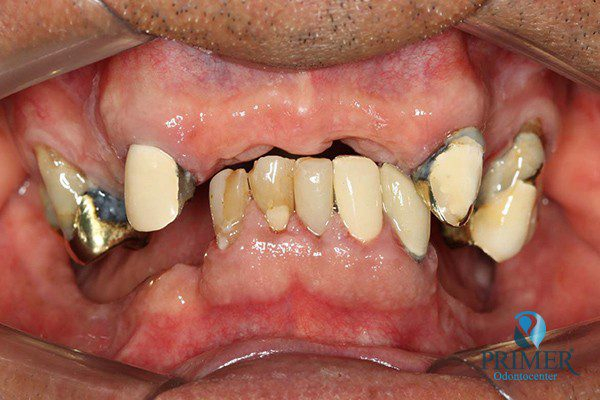

- Antes

- Sorriso inicial